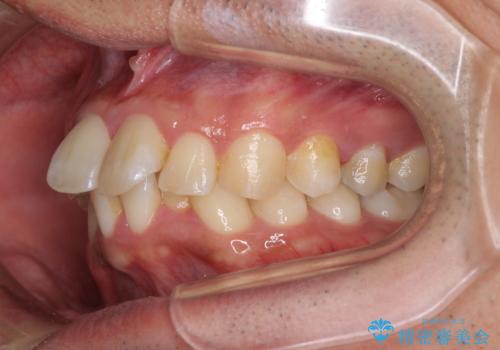

飛び出した前歯を治したい ワイヤー装置での抜歯矯正

- 上下ともに前歯2本が著しく飛び出している状態を気にして来院された患者様です。

唇の閉じにくさが認められたため、上下左右の小臼歯を1本ずつ、計4本を抜歯してワイヤー装置にて矯正治療を行うこととしました。

左上は、定石として抜歯される第一小臼歯の代わりに、神経が除去されている第二小臼歯を抜歯することとしました。

セオリーから外れた治療となるため、補助装置などを使用してよりよい仕上がりを目指すこととしました。

第二小臼歯を抜歯したことだけでなく、非常に強い咬合力もあり、治療期間は非常に長期となりましたが、しっかりと仕上げることができました。